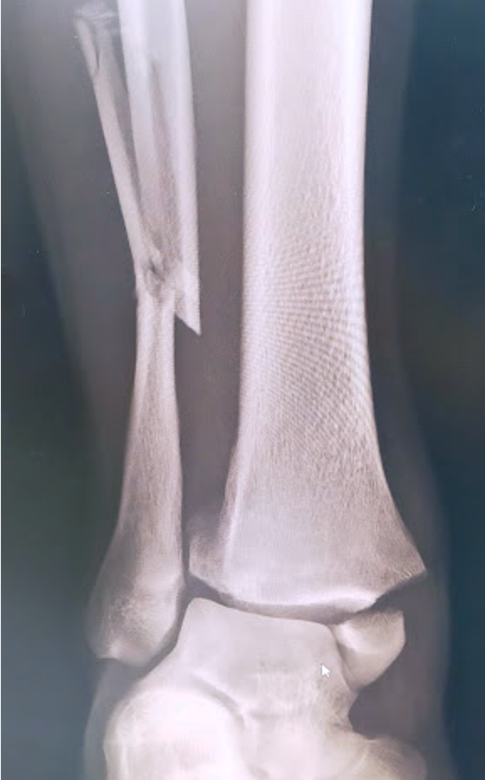

ひざ、股関節を含む、四肢の骨折に対しては、適応があれば手術加療を行い、機能改善および早期の社会復帰を目指しています。

関節を含む骨折は、機能障害を起こしやすく、正確に関節を再建する必要があり、早期リハビリ、機能改善にはとても重要です。

その他、上肢の骨折、足関節や下腿骨などの下肢骨折など、日常的に発生することの多いほとんどの骨折に対する治療に対応しています。

足関節脱臼骨折に対する骨接合術